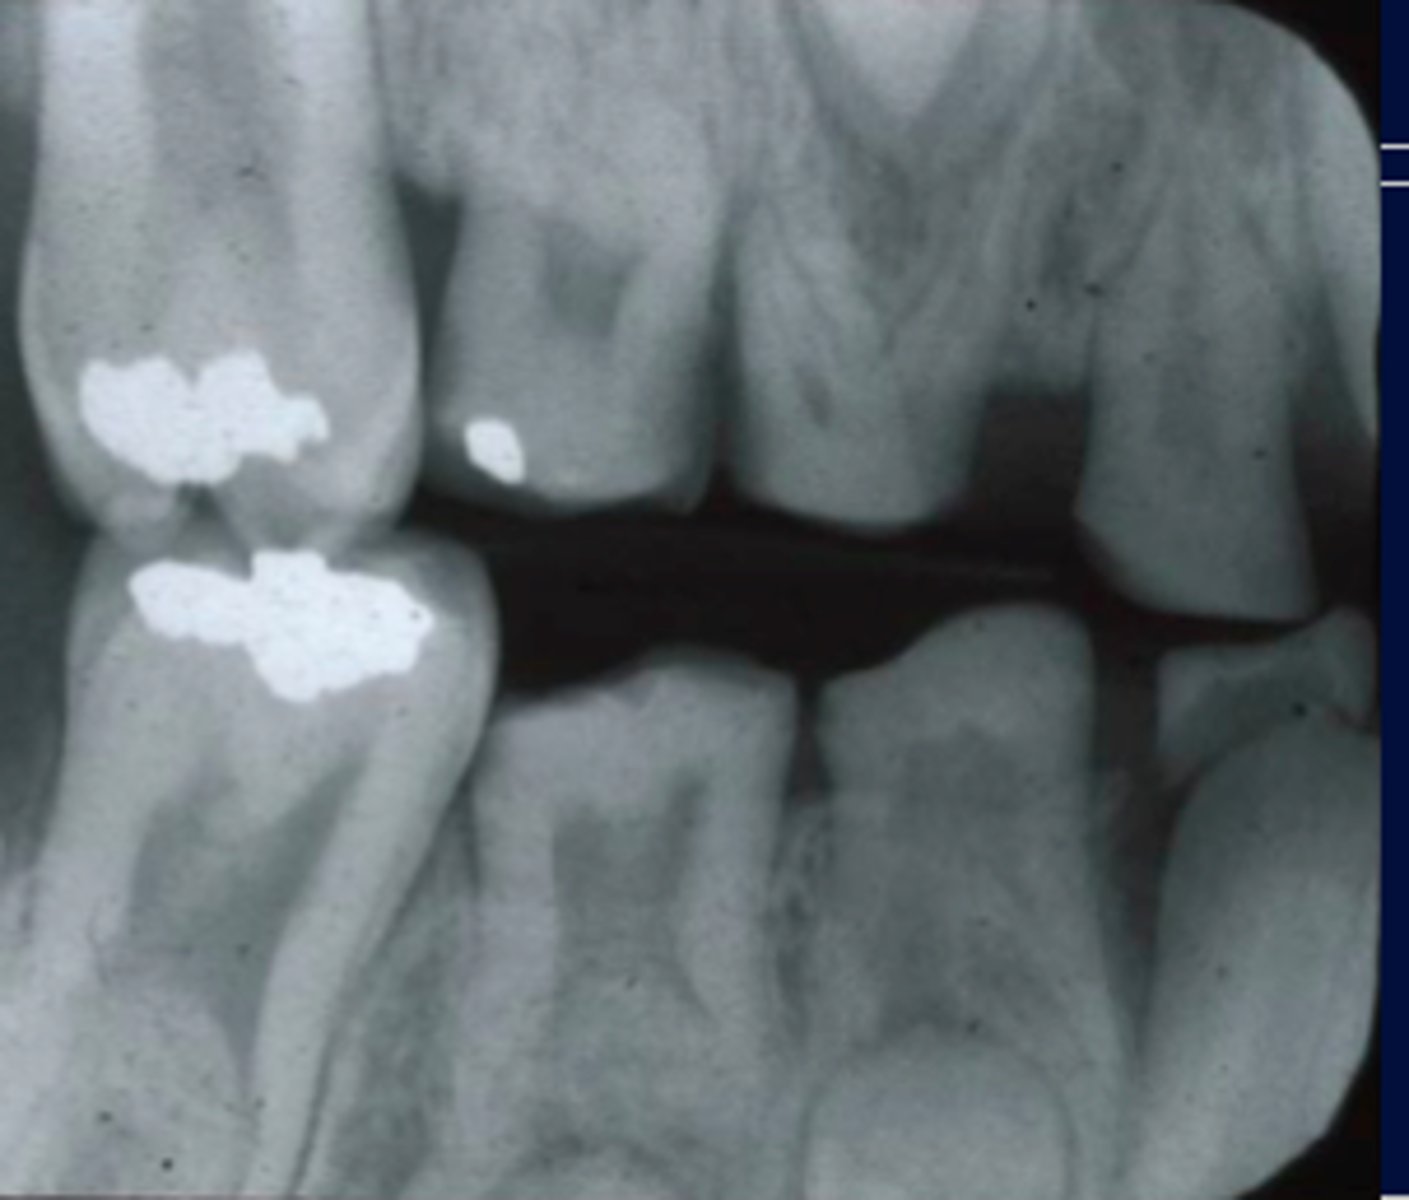

patient has no enamel on the teeth on bitewing or panx

amelognesis imperfecta

can see OBLITERATED pulp chambers on radiogrpahs and teeth have a TRANSLUCENT or opalescent hue (greyish or blue)

also known as osteogenisis imperfect

associated with collagenn maturation problem, non systemic

dentogenisis imperfecta